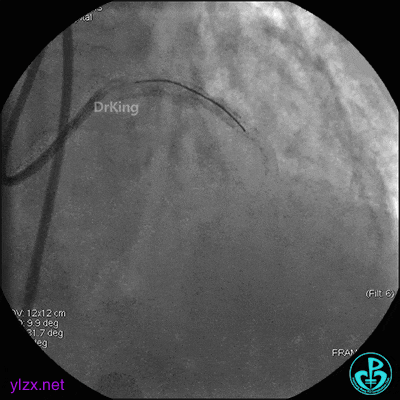

4 急诊冠脉造影

左主干轻度狭窄,左主干到前降支近端钙化影明显。前降支开口严重狭窄,近端闭塞。粗大回旋支轻度狭窄。

右冠脉无严重狭窄,右冠脉没有给前降支提供逆向供血。

5 治疗过程

EBU指引导管到位,导丝通过闭塞段到达前降支远端,经指引导管冠脉内推注替罗非班6ml,前降支恢复3级血流,闭塞段局部残余狭窄严重,2.0×15mm球囊扩张前降支近端闭塞处后再次冠脉内推注替罗非班8ml。下台继续治疗。